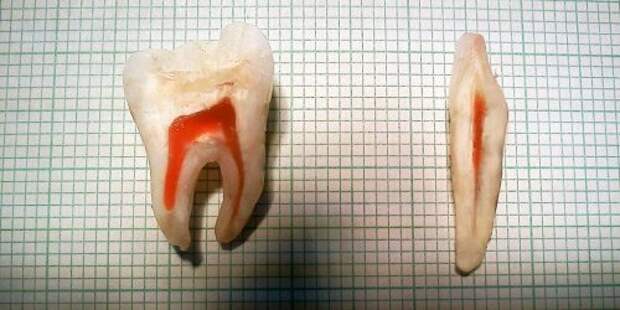

Зуб человека